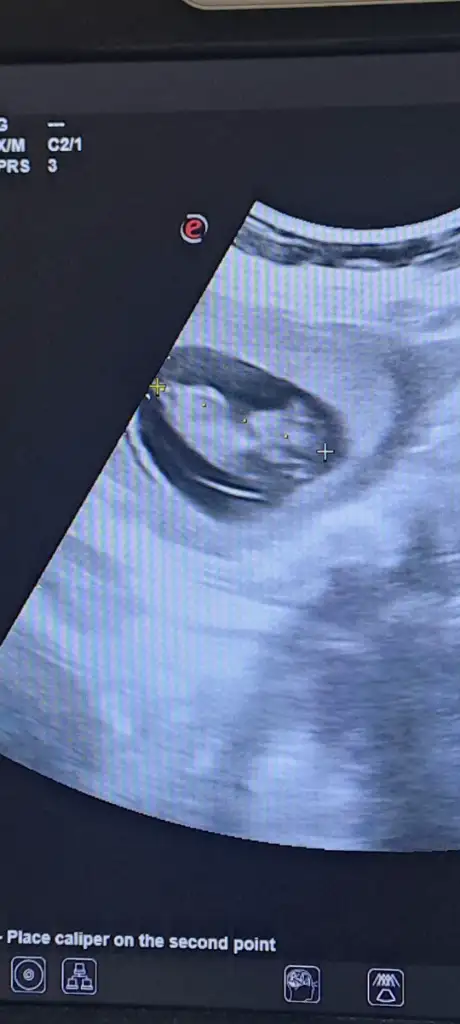

Merhabalar burda bebeğim 14 haftalık. 12 haftalıkken bir doktor kıza benziyor dedi kemik yapısı. 14 hafta başka bir doktor çıkıntı var erkek olabilir dedi alışveriş yapma bekle ama eğer bu gördüğüm pipisi değilse kızdır dedi keism gibi konuştu başta ama sonra alışveriş yapmayın 19 haftada gidince kesin söyleyecek. Sizce degisr mi cinsiyeti merak ediyorum?

Eklentiler

• 1000065546.webp

1000065546.webp

17 KB · Görüntüleme: 60